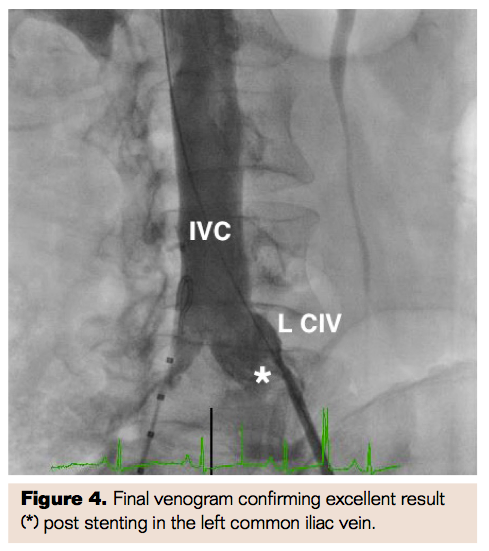

A 5 Fr Omni Flush catheter (Angiodynamics) was advanced through the right CFV and positioned at the left CIV-IVC junction. A 12 mm x 20 mm Mustang balloon (Boston Scientific) was advanced through the left CFV and inflated to predilate the left CIV. A 14 mm x 40 mm Protégé stent (Covidien) was deployed in the IVC, extending across the lesion in the left CIV and postdilated using the same balloon with excellent venographic result (Figure 4). The patient tolerated the procedure well and was discharged home the following day with dual antiplatelet therapy for at least 3 months.